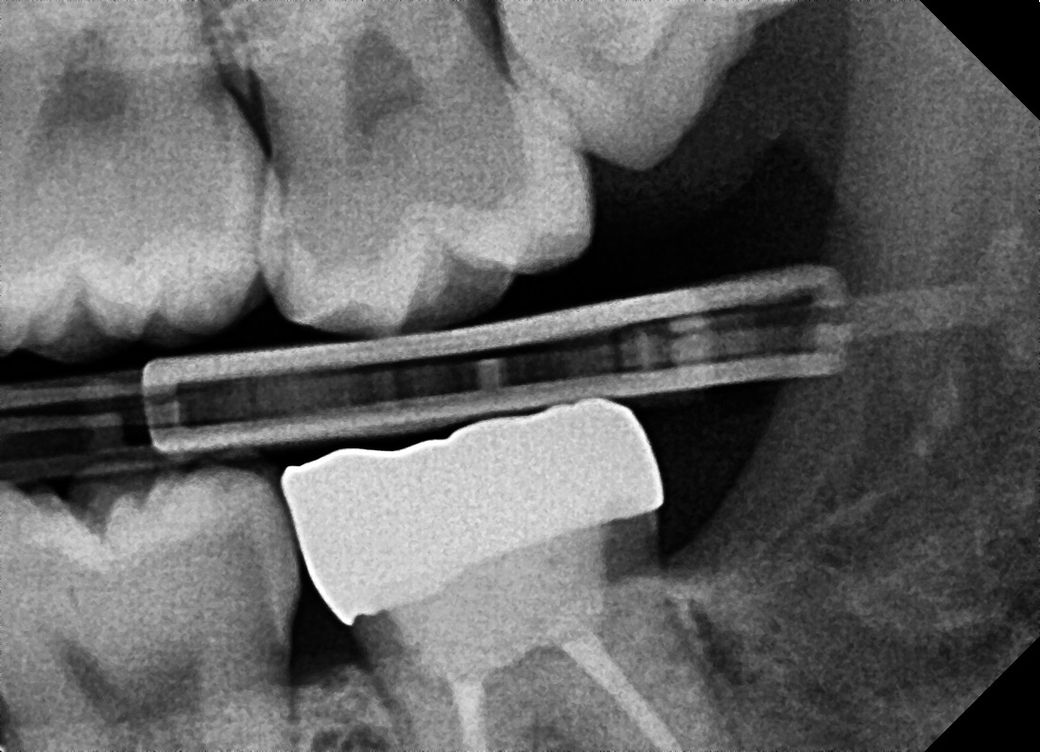

치과 의견이 너무 다릅니다.. 인접면 충치 관련 알려주세요

오늘 2개 치과를 다녀왔는데 말이 너무 반대라서 어떤치료를 해야할지 모르겟어요

사진도 제일 많이 찍고 엑스레이사진이 제 주관상 가장 좀 선명?했습니다 인접면 충치가 9개 정도 모인다고 최소 198만원에서 271만원으로 인레인, 레진 치료를 해야한다고 합니다

인접면 충치는 신경치료 가능성이 높아서 바로 치료해야 한다고 합니다

사진은 a치과 엑스레이 사진입니다!

엑스레이 상으로는 인접면에 충치가 많이 있는걸로 보입니다. 일단 3개월정도 관리를 해보고 그때 가셔서 충치가 진행되면 치료를 진행하시고 관리가 잘되면 계속해서 관리를 해볼것같습니다.

정확한 검사는 따로 해봐야 겠으나 사진상으로는 명확히 충치가 여러군데에서 진행되고 있습니다.

방사선 사진상으로는 작은 충치가 보이긴 하지만 정확한 확인을 위해서는 육안으로 확인을 해야 합니다. 하지만 방사선 사진상으로는 그렇게 큰 충치는 보이지 않습니다.

작은 충치의 경우 관리를 하면 진행이 멈추는 경우도 있습니다.

B 치과 말이 맞습니다. 충치 조금 있는 것은 지켜 보다가 더 진행되면 해도 됩니다. 아마도 A치과는 상담원이 상담했을 가능성도 있습니다.